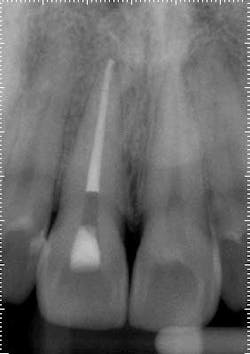

Treatment: Upon access, a necrotic pulp was identified. The dentin triangle was removed with a series of Gates-Glidden burs. Copious irrigation was completed with sodium hypochlorite. The canal was instrumented with stainless steel hand files and rotary ProFile series 29, both 0.04 and 0.06 taper. The canal was filled with a warm vertical downpack and thermoplasticized gutta-percha backfill. To maximize esthetics, the space was underfilled to the level of the crestal bone to prevent staining the chamber.